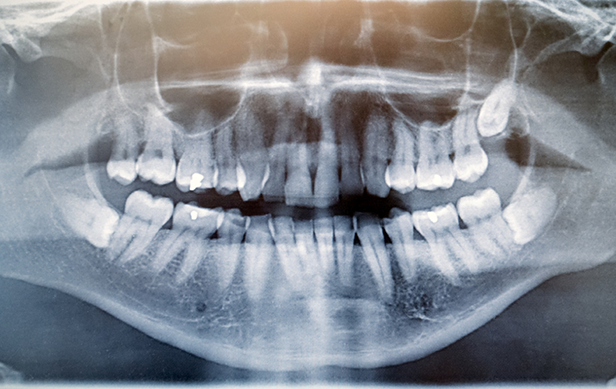

Before we schedule a wisdom tooth extraction procedure for any of our patients, we do a consultation first. During your consultation, we’ll examine diagnostic images of your mouth and speak with you about your symptoms. If we determine that your wisdom teeth need to be removed but they’re still impacted below the gumline, a surgical extraction may be necessary. This involves our team creating a small window in the gumline that will allow us to access the impacted tooth, divide it up into smaller pieces, and remove each of the pieces. However, if the wisdom teeth have erupted, we can complete a simple extraction by lifting them out of their sockets.